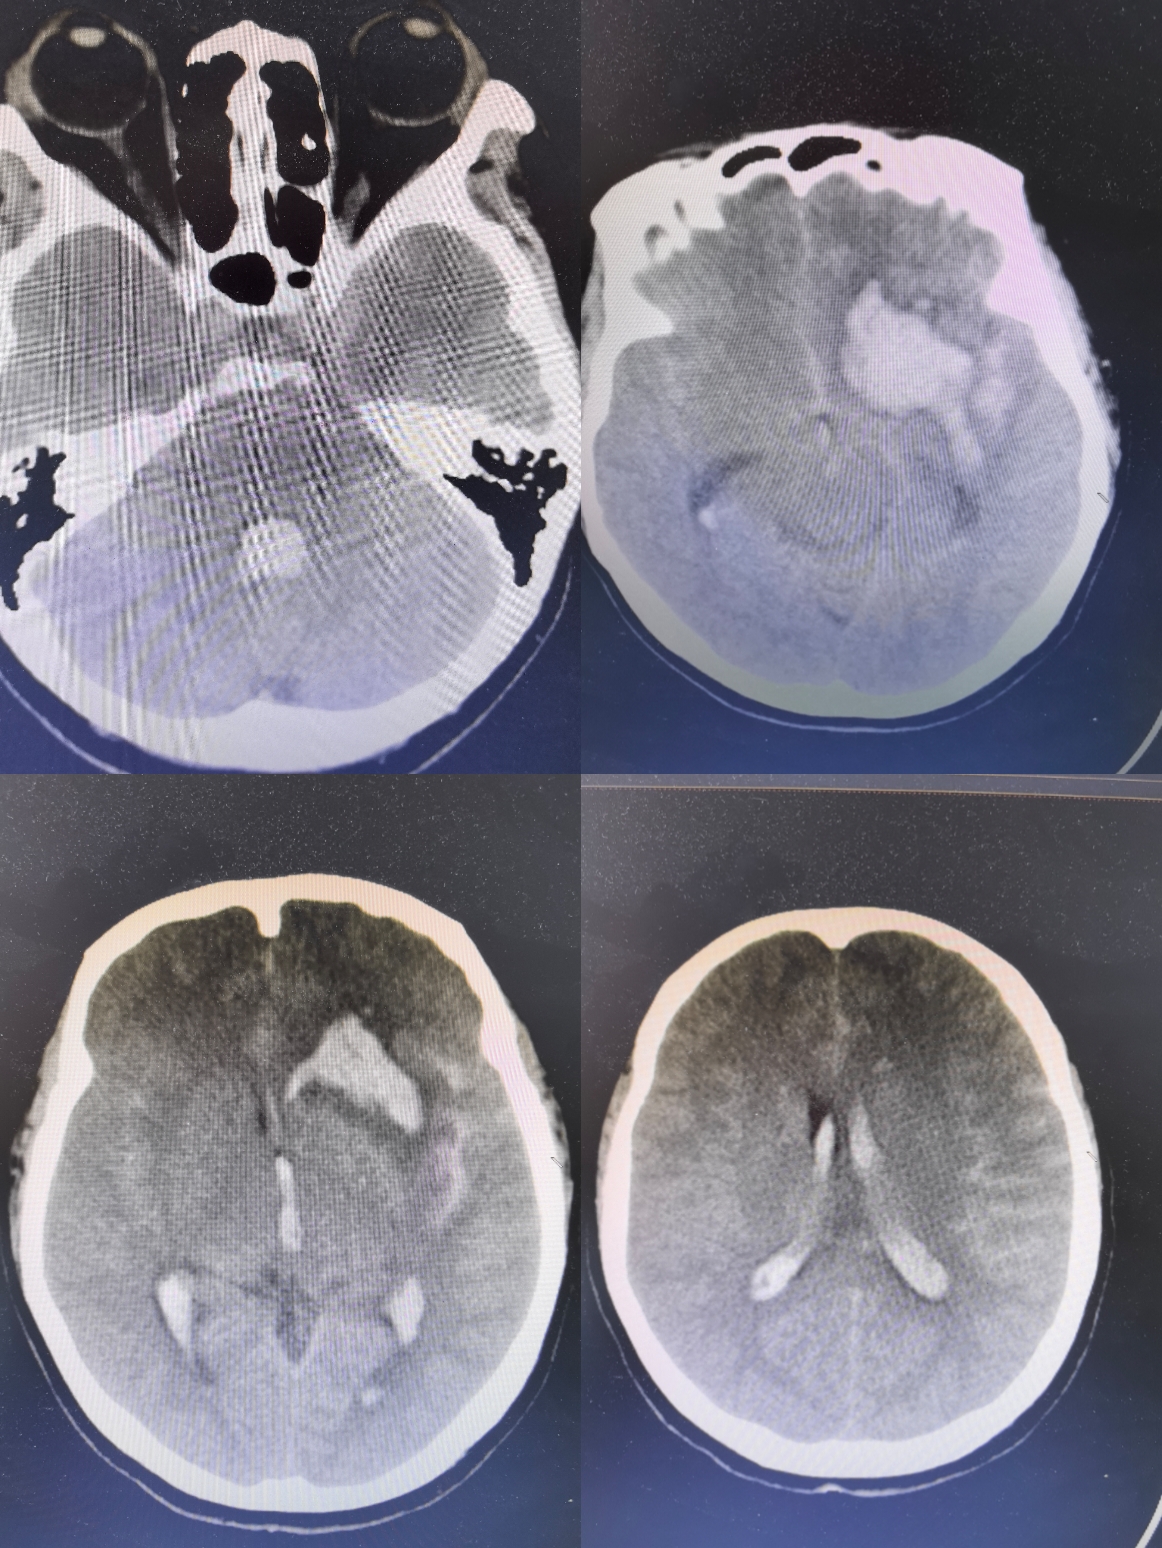

姜xx,女,53岁,主诉:突发头痛伴呕吐8小时,既往健康,查体:浅昏迷GCS8分,刺痛睁眼,无发音,双上肢定位,颈强阳性,。

头CT显示蛛网膜下腔出血破入脑室及脑内,三四脑室铸型

CTA阴性